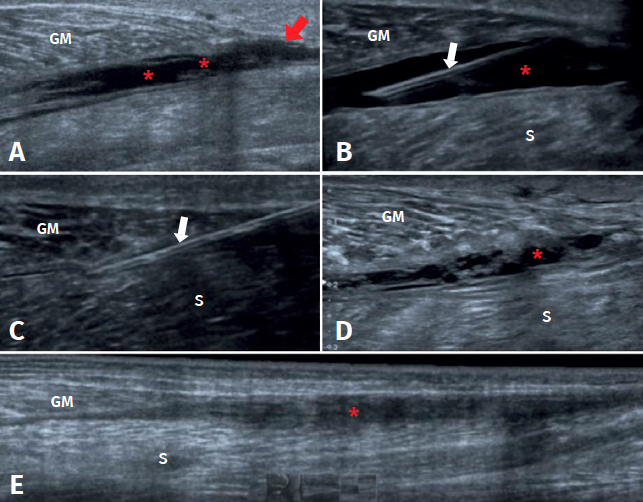

Ultrasound is the initial imaging technique of choice, due to its rapid accessibility, low cost and the absence of radiation(26,27,28), as reflected in Figure 1. Some of the features to be evaluated by ultrasound are the size of rupture, whether rupture is total or partial, and the presence of haematoma and/or fluid collections between the gastrocnemius and the soleus.

Figure 1. Ultrasound study of triceps surae injuries. A: fibrillar damage of the distal myotendinous junction of the medial gastrocnemius muscle, showing the hypoechogenic fibrillar defect (arrow) associated to loss of the usual fibrillar pattern and oedema of the adjacent muscle fibres (asterisk); B: distal myotendinous junction of the medial gastrocnemius in a normal triceps surae muscle.

The most frequent ultrasound finding in triceps surae muscle injuries is a hypoechogenic zone at the distal myotendinous junction of the medial gastrocnemius muscle(29). The latter appears as a serohematic content between the muscle fibres and the myofascial plane, associated to an increase in echogenicity of the adjacent musculature as a manifestation of oedema and hyperaemia in the colour Doppler study(9), as can be seen in Figure 1. Delgado et al., in 141 patients clinically diagnosed with tennis leg, found that 67% of the patients presented partial rupture of the medial gastrocnemius, 1.4% presented associated plantaris tendon rupture, and 21% presented an intermuscular fluid collection between the medial gastrocnemius and the soleus muscle - thus affording an improved perspective of the possible differential diagnosis(30). On the other hand, involvement of the lateral gastrocnemius is much less common (up to 14% of the cases)(31). Ultrasound also plays a role in the lesions follow-up. In a normal evolutive scenario, we can observe gradual reduction of the oedema, resolution of the fibrillar defect and reabsorption of the fluid collections(32). It is also common to observe signs of organization of the haematoma between the gastrocnemius and the soleus, evolving as a fusiform fibrous scar without inflammatory elements, as can be seen in Figure 2.